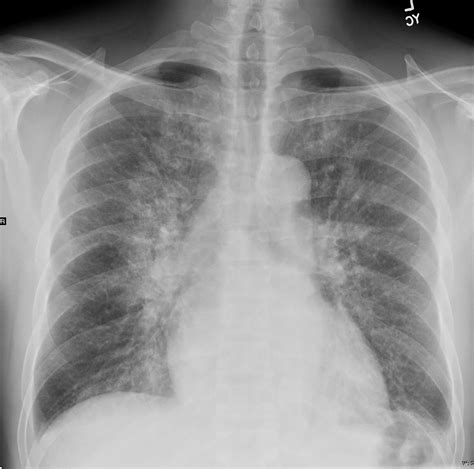

Once the Pulmonary Edema Cxr confirms the diagnosis, management usually involves the administration of loop diuretics, vasodilators, and oxygen therapy. The imaging serves as a baseline to monitor the patient's response to therapy. Following treatment, a repeat chest X-ray is often ordered to observe the "clearing" of the lung fields, which usually occurs as the patient achieves a negative fluid balance.

Persistent opacities despite adequate diuresis may suggest complications such as pneumonia, lung collapse, or a non-cardiogenic component to the pulmonary edema. Regular assessment through imaging ensures that the treatment plan is effectively targeting the underlying cause of the fluid overload.

In summary, the diagnostic power of the chest X-ray remains unmatched for its accessibility and speed in clinical environments. By identifying specific signs like cephalization, Kerley B lines, and alveolar opacities, healthcare providers can swiftly categorize the severity of pulmonary edema. While the Pulmonary Edema Cxr is a cornerstone of diagnosis, it must be interpreted alongside clinical symptoms and hemodynamic markers to ensure accurate patient care. Through systematic evaluation and an understanding of the radiographic progression of fluid accumulation, clinicians can effectively manage fluid overload and improve patient outcomes in high-stress, acute care settings.